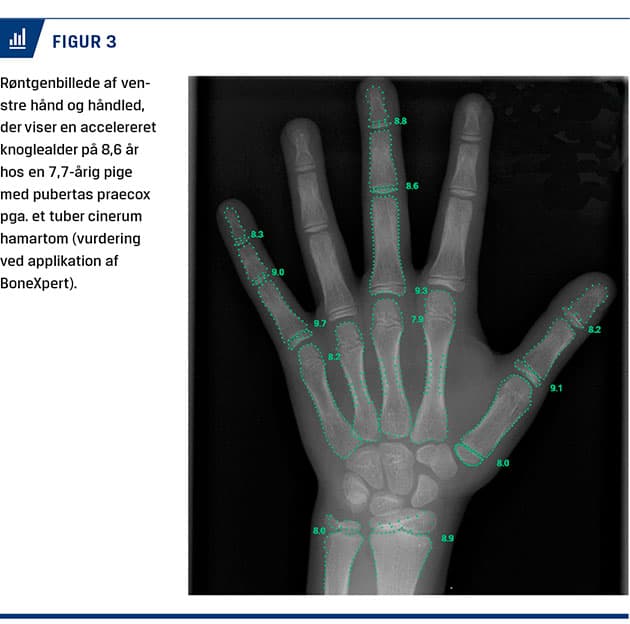

Der laves røntgenoptagelse af venstre hånd for knoglealderbestemmelse (BA) (Figur 3). Ved PP er BA typisk avanceret i forhold til den kronologiske alder pga. epifysernes følsomhed for østrogen [9]. Der tages blodprøver (Tabel 1). Ved mistanke om CPP udføres der en stimulationstest med GnRH-test [2, 16]. Små piger < 3 år har højere stimulerede LH-værdier helt op til 9,2 IE/l end større piger pga. minipuberteten [28]. LH-FSH-ratio er derimod ikke aldersafhængig. Ultralydskanning af genitalia interna er brugbar som led i udredningen, da vækst af uterus og ovarier sker forud for udviklingen af sekundære kønskarakteristika [12]. Hvis undersøgelserne bekræfter CPP, skal der udføres MR-skanning af cerebrum med fokus på hypothalamus og hypofyselejet [10]. I et dansk studie med 208 piger med tidlig pubertet eller CPP uden CNS-symptomer sås der abnorme fund på MR-skanning af cerebrum hos 33 (15,9%) [29]. Hos 13 vurderedes MR-skanningsforandringerne at være den udløsende årsag, hvorimod forandringerne i 20 tilfælde blev betragtet som tilfældige fund. Derfor er undersøgelse altid nødvendig.